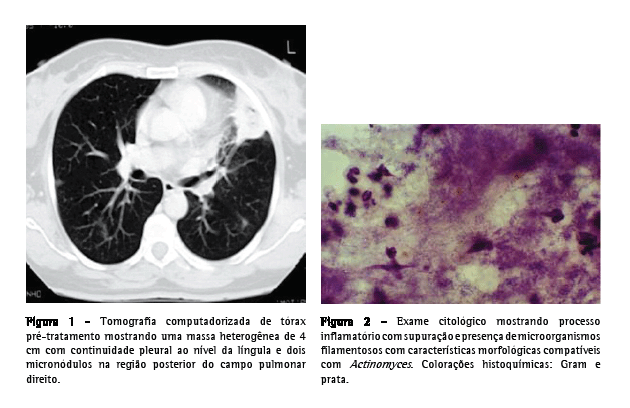

Uma paciente do sexo feminino, 55 anos de idade, caucasiana, não fumante, secretária, procurou atendimento no serviço de emergência. Tinha história de hepatite B crônica, hipertensão arterial, dislipidemia mista e múltiplas cáries dentárias não tratadas. Relatou que há três semanas havia iniciado quadro de dejeções diarréicas diárias, azia, desconforto retroesternal agravado pelo decúbito dorsal, astenia, anorexia e emagrecimento (5 kg). Uma semana depois haviam surgido toracalgia esquerda de características pleuríticas com agravamento progressivo, acessos freqüentes de tosse seca ao esforço e pico febril isolado. O eletrocardiograma foi normal, e a endoscopia digestiva alta revelou um cárdia complacente e gastrite antral. A telerradiografia de tórax mostrou hipotransparência heterogênea, esboçando perda de substância em seu seio, no terço médio do campo pulmonar esquerdo. A tomografia computadorizada de tórax evidenciou a presença de uma massa de 4 cm com conteúdo heterogêneo e continuidade pleural ao nível da língula e a presença de dois micronódulos subpleurais na região posterior do campo pulmonar direito (Figura 1). Procedeu-se ao estudo etiológico considerando-se a hipótese diagnóstica de neoplasia pulmonar como a mais provável. Do estudo analítico, salientam-se os seguintes resultados: velocidade de hemossedimentação = 98 mm/1a h; antígeno do câncer 125 = 63,3 U.mL-1 (<35,0); antígeno carcinoembriogênico = 3,55 ng.mL-1 (<2,5) e discreta elevação da proteína C reativa. O estudo imunológico sérico, os marcadores virais e o estudo analítico final não revelaram outras alterações relevantes. Os resultados da colonoscopia, da ultrassonografia abdominopélvica, da mamografia e da citologia cérvico-vaginal foram normais. A primeira fibrobroncoscopia realizada mostrou sinais inflamatórios difusos ao nível da língula. Os resultados do exame citológico de aspirado, lavado brônquico e lavado broncoalveolar foram negativos para células neoplásicas. O exame microbiológico em aerobiose foi também negativo, assim como a pesquisa de bacilos álcool-ácido resistentes. A paciente foi então submetida à biópsia aspirativa transtorácica (BAT), que, ao exame citológico extemporâneo, mostrou um processo inflamatório com supuração. Face a este resultado provisório, iniciou-se a antibioticoterapia com levofloxacina 500 mg via oral ao dia, e decidiu-se realizar uma segunda fibrobroncoscopia. Entretanto, o exame citológico da BAT revelou aspectos morfológicos compatíveis com a presença de Actinomyces, confirmada pelo exame microbiológico cultural do lavado brônquico e broncoalveolar da segunda fibrobroncoscopia, no qual se identificou A. naeslundii (Figura 2). A pesquisa de bacilos álcool-ácido resistentes foi negativa. Dada a melhoria clínica e radiológica após um mês de tratamento (Figura 3), optou-se por manter a antibioticoterapia já iniciada, cuja posologia foi alterada: levofloxacina 500 mg endovenoso ao dia por quatro semanas e, depois, 500 mg po qd. Não se verificou iatrogenia à terapêutica, a qual foi mantida por 16 semanas, até a completa normalização radiológica. Analiticamente constatou-se uma redução da velocidade de hemossedimentação e uma redução de ambos os marcadores tumorais inicialmente alterados, assim como a normalização da proteína C reativa. A paciente foi também submetida a tratamento dentário.

A opção terapêutica utilizada no presente caso foi incontestavelmente controversa mas, tendo sido iniciada com eficácia clínica antes da confirmação diagnóstica, foi mantida, com o consentimento informado da paciente, até a regressão da sintomatologia e normalização completa das alterações radiológicas. A evolução desse caso sugere que a levofloxacina representa uma alternativa ao tratamento convencional da actinomicose pulmonar.